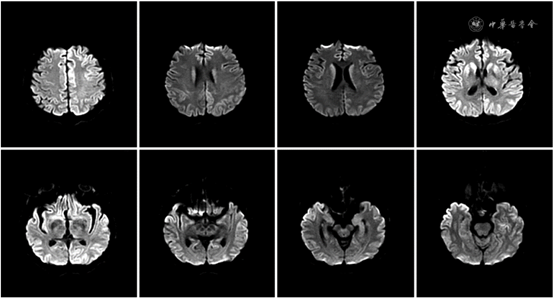

2020年12月15日头颅MRI示右侧额颞顶枕叶、左侧额叶、右侧尾状核头可见DWI高信号(见图1)。考虑患者目前存在突出的进行性认知功能下降、锥体外系及锥体束受损症状、异常头颅MRI表现,建议就诊于神经内科进一步排除引起快速进展性痴呆相关神经系统变性疾病,故于2020年12月15日转诊至外院就诊。

图1 2020年12月15日患者头颅MRI示右侧额颞顶枕叶、左侧额叶、右侧尾状核头可见DWI高信号